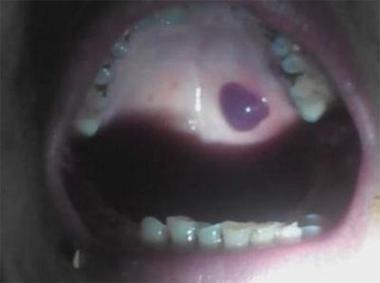

口腔内壁突然长黑色泡是何原因?

口腔内壁的黑色泡状物,根据其性质(是液体还是组织),颜色(是纯黑还是深紫色),以及是否疼痛,可能指向以下几种情况:

外伤性血疱 (最常见)

- 成因:这是最常见的原因之一,可能是因为吃饭时不小心咬到、吃硬物(如薯片、坚果壳)划伤、或者佩戴不合适的假牙、牙套摩擦导致的局部毛细血管破裂出血。

- 外观:疱壁薄,内部充满血液或暗红色的血液凝块,所以看起来是深红色、紫色或接近黑色的泡,通常发生在咀嚼、摩擦频繁的区域,如颊黏膜(内壁)、舌侧等。